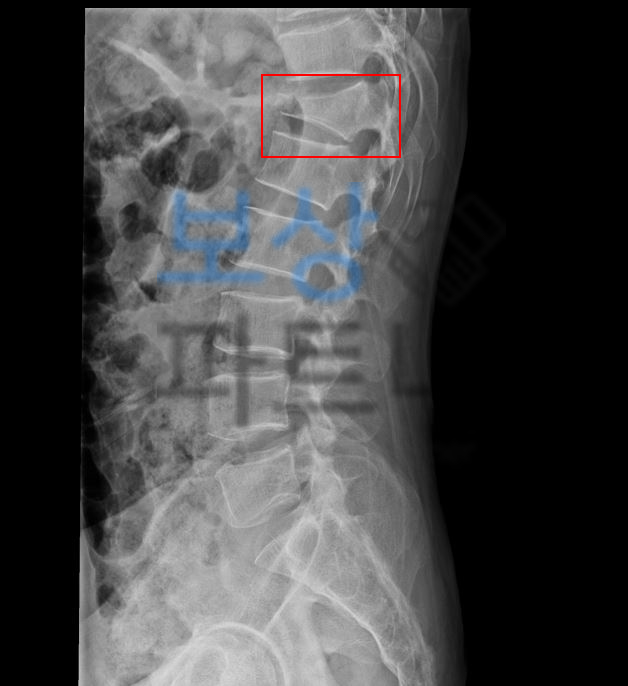

spinal fixation of T10 ~ L2

흉추10번 ~ 요추2번 척추고정, 유합술

척추12번 골절 사진

한@@님은 일하던 현장에서 추락사고를 당하셔서 척추뼈 골절을 진단받게 되었습니다. T12 흉추12번 골절 뿐 아니라 척수 손상도 동반되었고 척추유합술 실시하게 되었는데요,